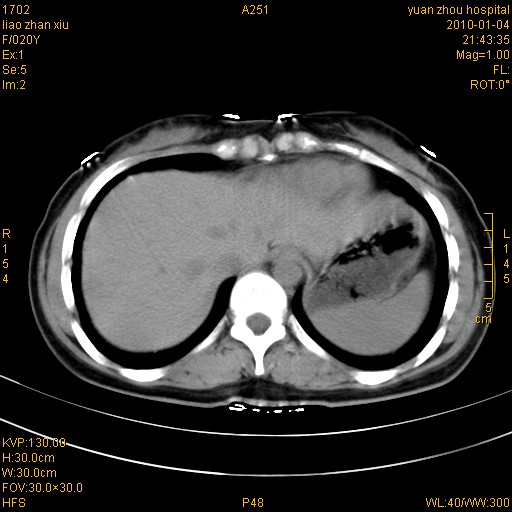

标题: CT23985:F20Y 外伤典型病例 [打印本页]

标题: CT23985:F20Y 外伤典型病例

左肾挫伤,包膜下积血。

左肾挫裂伤伴肾被膜下积血!另:肾周筋膜增厚!

1)左肾包膜下血肿。2)左侧肾挫伤可能;建议:行ct增强扫描检查。3)腰椎左侧横突骨折。

左肾挫伤,包膜下积血,l3、4左侧横突多发骨折。

双侧肾胞膜下出血,左侧较多。l3、4左侧横突多发骨折。

1、左肾挫伤,包膜下积血;

2、l3、4左侧横突多发骨折;

3、腹腔积气,考虑肠管破裂?

左肾挫伤,包膜下积血,L1、2、3、4左侧横突多发骨折。